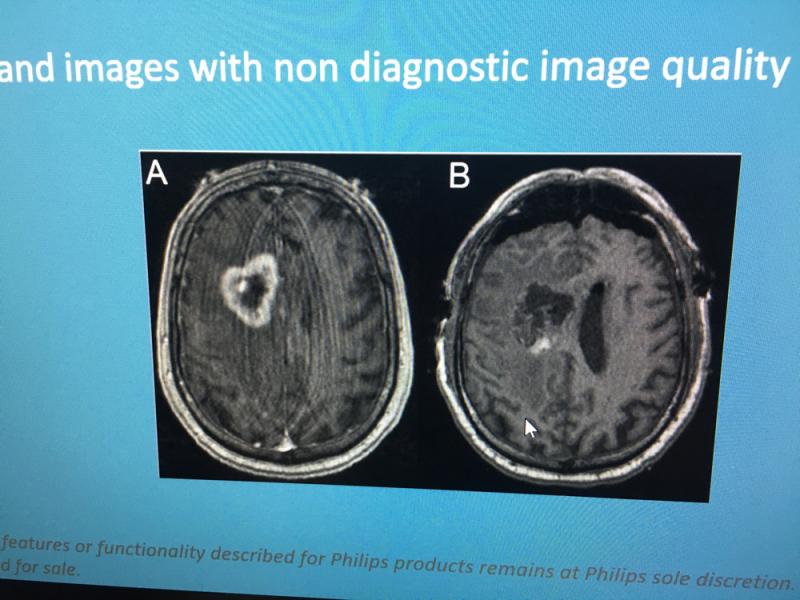

Here are images of some of the newest new medical imaging technologies displayed on the expo floor at the Radiological Society of North America (RSNA) 2019 meeting. Use the slider images below to see the photos.